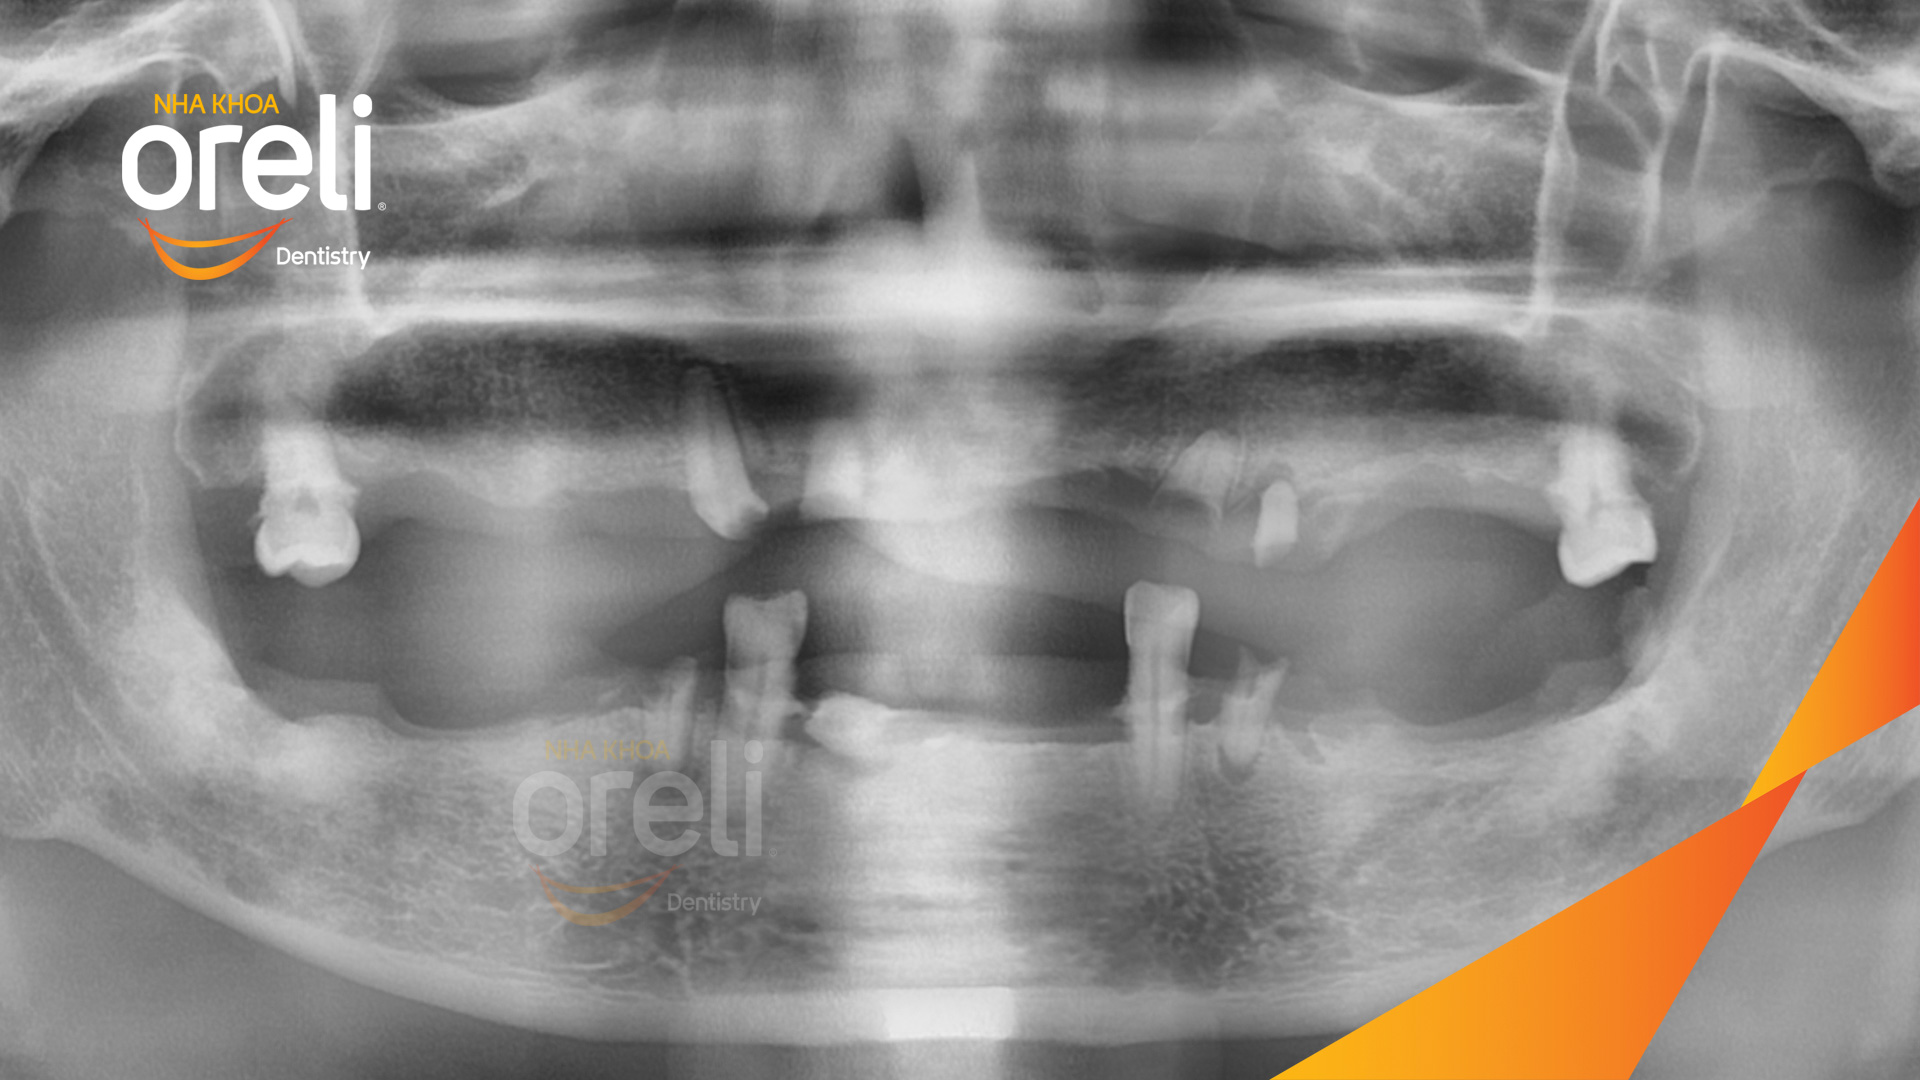

Tình trạng: Mất răng toàn bộ hàm trên và hàm dưới

Hình ảnh thực tế